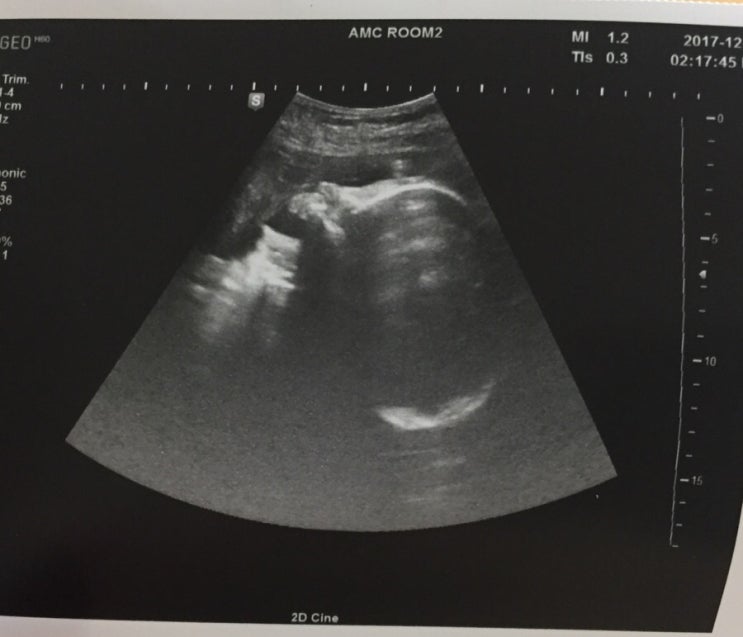

2017.12.27 35w1d

두근두근 제왕절개 날잡는 진료일엄청 마니자란 심쿵이 2.8kg 이라니 .. !! 촘파안에 얼굴이 꽉찼당 내눈에...